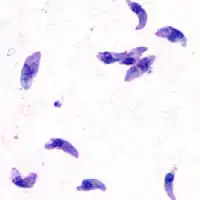

T. gondii is an apicomplexan parasite that can cause infection in humans. The parasite can live in many mammals and birds, but it carries out the sexual part of its lifecycle in cats. Feline feces from infected cats or undercooked meat from infected livestock contain T. gondii oocysts. Ingesting these could lead to Toxoplasmosis, a disease which at its worst can cause encephalitis or miscarriage as the disease is passed from mother to fetus.

T. gondii and other apicomplexan parasites rely on actin-dependent gliding motility in order to gain access to the body. This form of cellular motion requires profilin, an actin filament binding protein that helps restructure the actin cytoskeleton. Without profilin, T. gondii can still grow and replicate, but it loses the ability to pass through cell layers and biological barriers in order to carry out infection. Thus profilin is a conserved, essential protein for T. gondii infection efficacy.[12]